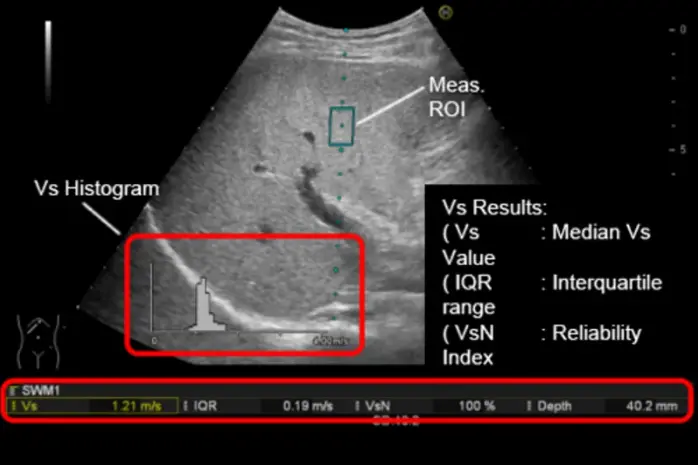

- Measurement of the propagation speed of waves within tissue, generated by a

high-frequency impulse (e.g., Shear Wave Elastography) or through Transient Elastography, commonly used for liver stiffness assessment.